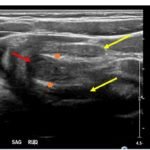

The patient’s abdominal ultrasound revealed intussusception in the right upper abdominal quadrant. The transverse ultrasound view showed a “doughnut sign” (dashed yellow line), telescoping bowel (yellow arrow), and invaginated hyperechoic mesenteric fat with crescent configuration (dashed orange line). The sagittal ultrasound view demonstrated the intussusception formed by the outer recipient bowel loop (yellow arrows), invaginated hyperechoic mesenteric fat (orange asterisks), and telescoping bowel centrally (red arrow).

Ultrasonography should be the initial imaging modality in cases with clinical suspicion for intussusception.4 Previously, contrast enemas were often used as a diagnostic tool and treatment modality. Studies have demonstrated that the modality choice had been related to age, with infants less than six months more likely to undergo enema while children greater than four were more likely to have a computed tomography scan or ultrasound.5 In the pediatric population, ultrasound has a sensitivity of 97.9% and specificity of 97.8% for diagnosis of ileocolic intussusception.6 A “doughnut,” “pseudokidney,” or “target sign” are diagnostic findings.3,7 The study could be performed by radiology or at the bedside in the ED.8,9 A study reported that with limited training, ED physicians could accurately perform ultrasound to diagnose intussusception, with a sensitivity of 85% and a specificity of 97%. Further studies are needed to determine the utility of bedside ultrasound for the diagnosis of intussusception in the community setting.3